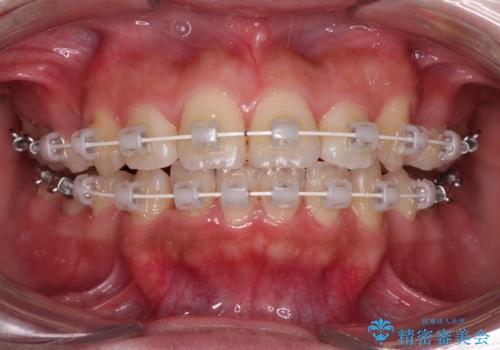

- 矯正装置

- 審美装置

- 2年1ヶ月

- 10-30回